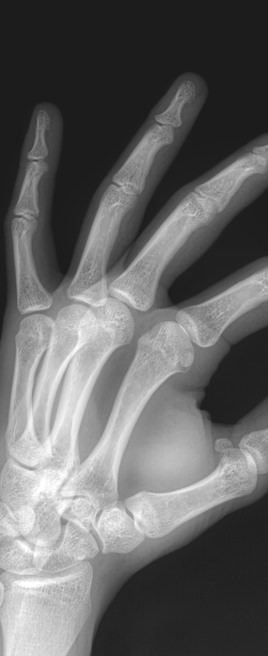

Все изменения хорошо видны на рентгеновском снимке, он и будет первым, а чаще и основным, видом диагностики. Основываясь на рентгенограмме, а также лабораторных показателях, врач выбирает оптимальное лечение и дальнейшее ведение болезни.

На прицельном снимке будут отчетливо видны следующие изменения:

• Суставная щель может быть расширена, в том числе неравномерно, или сужена, в ней обнаруживается выпот или участки обызвествления;

• Суставные поверхности могут не соответствовать друг другу из-за вывиха;

• В тканях кости и надкостницы обнаруживаются участки разрежения, уплотнения, разрастания, воспаления, перелома;

• Утолщение мягких тканей;

• Новообразования, при наличии.